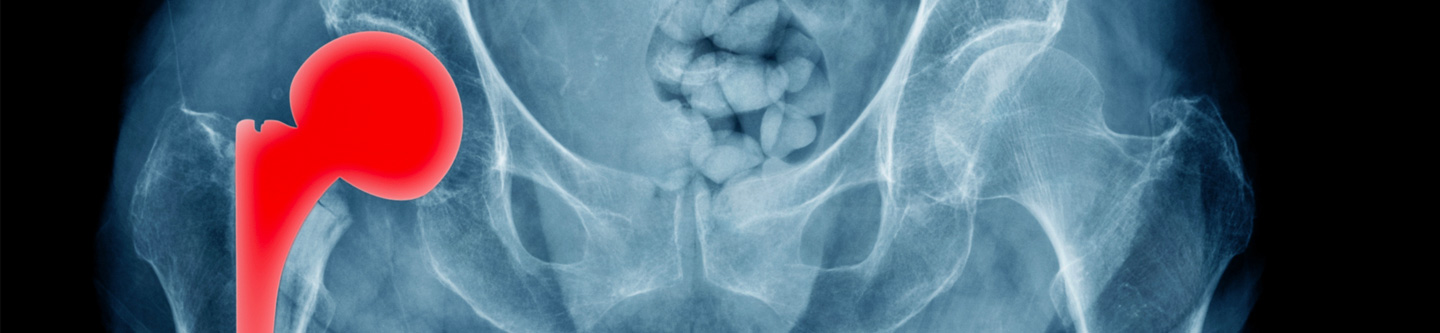

Joint Replacement

The physicians at First State Orthopaedics have extensive experience and knowledge in the diagnosis, treatment, and management of all conditions of the hip, knee, and shoulder. Our fellowship trained surgeons specialize in the replacement of joints affected by arthritis, inflammatory conditions, and trauma. From preoperative education, through surgery, recovery, and rehabilitation, everything is designed for the special needs of our patients.

Our joint reconstruction team is at the forefront of outpatient total shoulder replacement, reverse shoulder replacement, total hip replacement, partial knee replacement, and total knee replacement. Our surgeons are proficient in all approaches for joint replacement, including direct anterior hip replacement. The First State Surgery Center is equipped to allow our surgeons the ability to perform procedures which safely allow patients to now recover in their own homes.